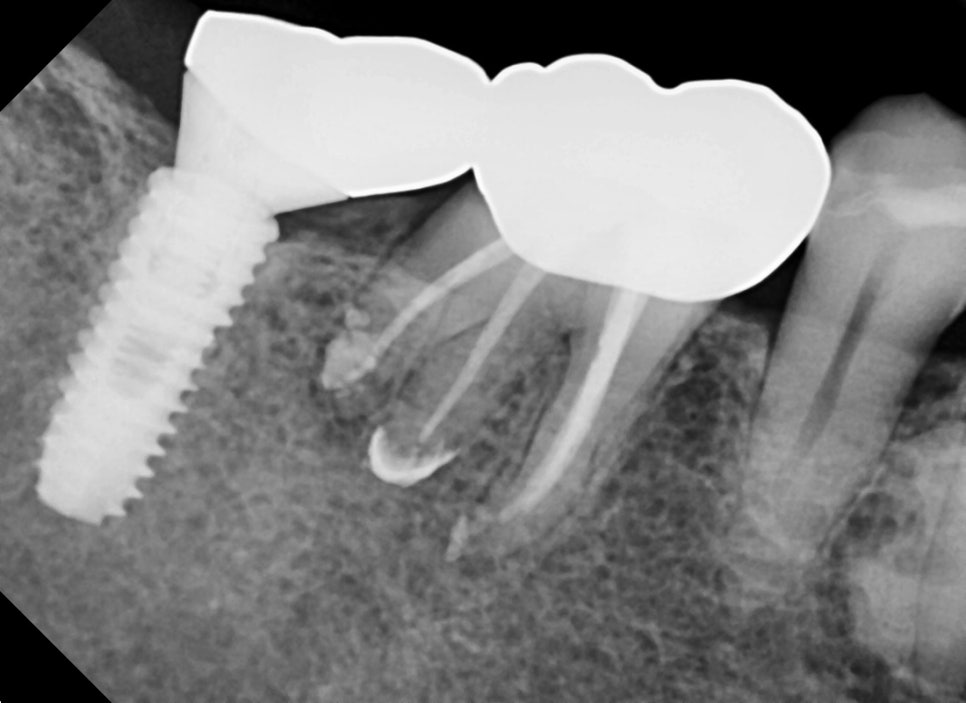

10개월이 지난 후 찍은 엑스레이 사진과 구내 사진입니다

증상은 치료 전과 비교했을 때 통증이나 불편감은 없으시다 하셨고

뿌리 주변의 염증소견도 나아진 상태입니다.

치료전 염증이 컸던 치아라 걱정하며 주기적으로 체크를 하는 중인데

다행히 잘 유지되고 있습니다.

신경치료가 마무리된 후 엑스레이 사진입니다.

첫 번째 케이스와 마찬가지로 의도하지는 않았지만

뿌리 쪽으로 충전재가 뿌리를 감사고 있는 모습을 보이고 있습니다.

염증에 의해 흡수된 치아 주변 뼈는 추후 천천히 차기를 기대해 보겠습니다.